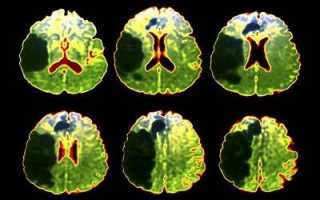

На первых порах для установки диагноза пациенту будет сделана магнитно-резонансная и / или компьютерная томография головы (в зависимости от предварительного диагноза, а также наличия соответствующего оборудования в клинике). Исследования понадобятся для того, что определить масштаб и локализацию поражения.

Пациент должен сразу же быть повергнуть обследованиям – МРТ и КТ головного мозга, чтобы определить, чем вызван и насколько распространен инфаркт. ЭКГ делается для анализа работы сердечно-сосудистой системы. Далее, общий анализ крови и выявление воспалительных процессов, уровня сахара в крови и т.п. Все это сочетается с программами нелекарственной реабилитации, описанными ниже.